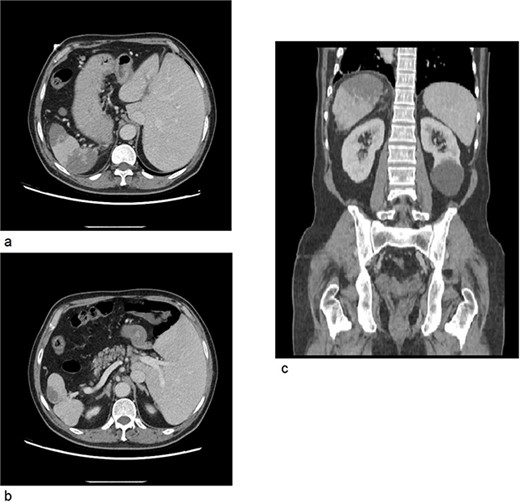

A computed tomography scan of the abdomen and pelvis with IV contrast was done (Fig. 2); situs inversus totalis was noted, large splenic infarcts were seen, and the superior mesenteric vein, splenic vein, and portal vein were patent. A 7.5 cm cyst was seen in the left kidney.

(a) CT axial cross section showing the liver on the left side of the abdomen and the spleen on right side with multiple splenic infarcts. (b) CT axial cross section showing patent splenic vein. (c) CT coronal cross section showing splenic infarcts as well as a left kidney cyst.